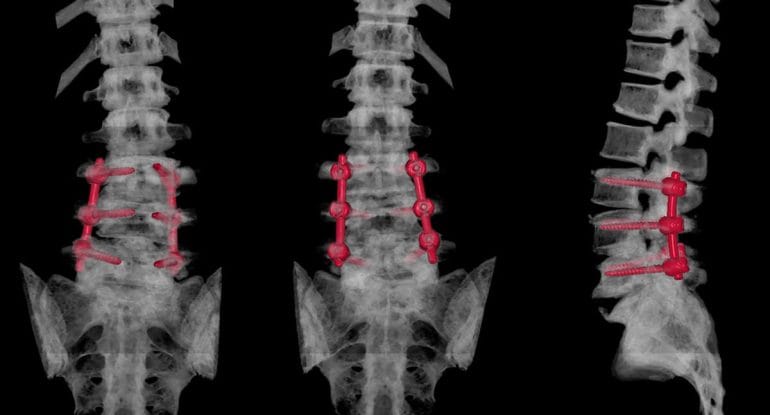

Spinal Surgery as an Outside In Approach

Spinal surgery is a classic Outside In approach to healthcare.

An Outside In approach attempts to fix pain by externally altering the body, such as removing tissue, replacing discs, or fusing joints, with the expectation that symptoms will resolve afterward.

However, for chronic disc-related pain, an Outside In solution often fails to restore full function because it does not address how the body adapts, compensates, and heals over time.

This is why many patients report that surgery changed their imaging but not their quality of life.